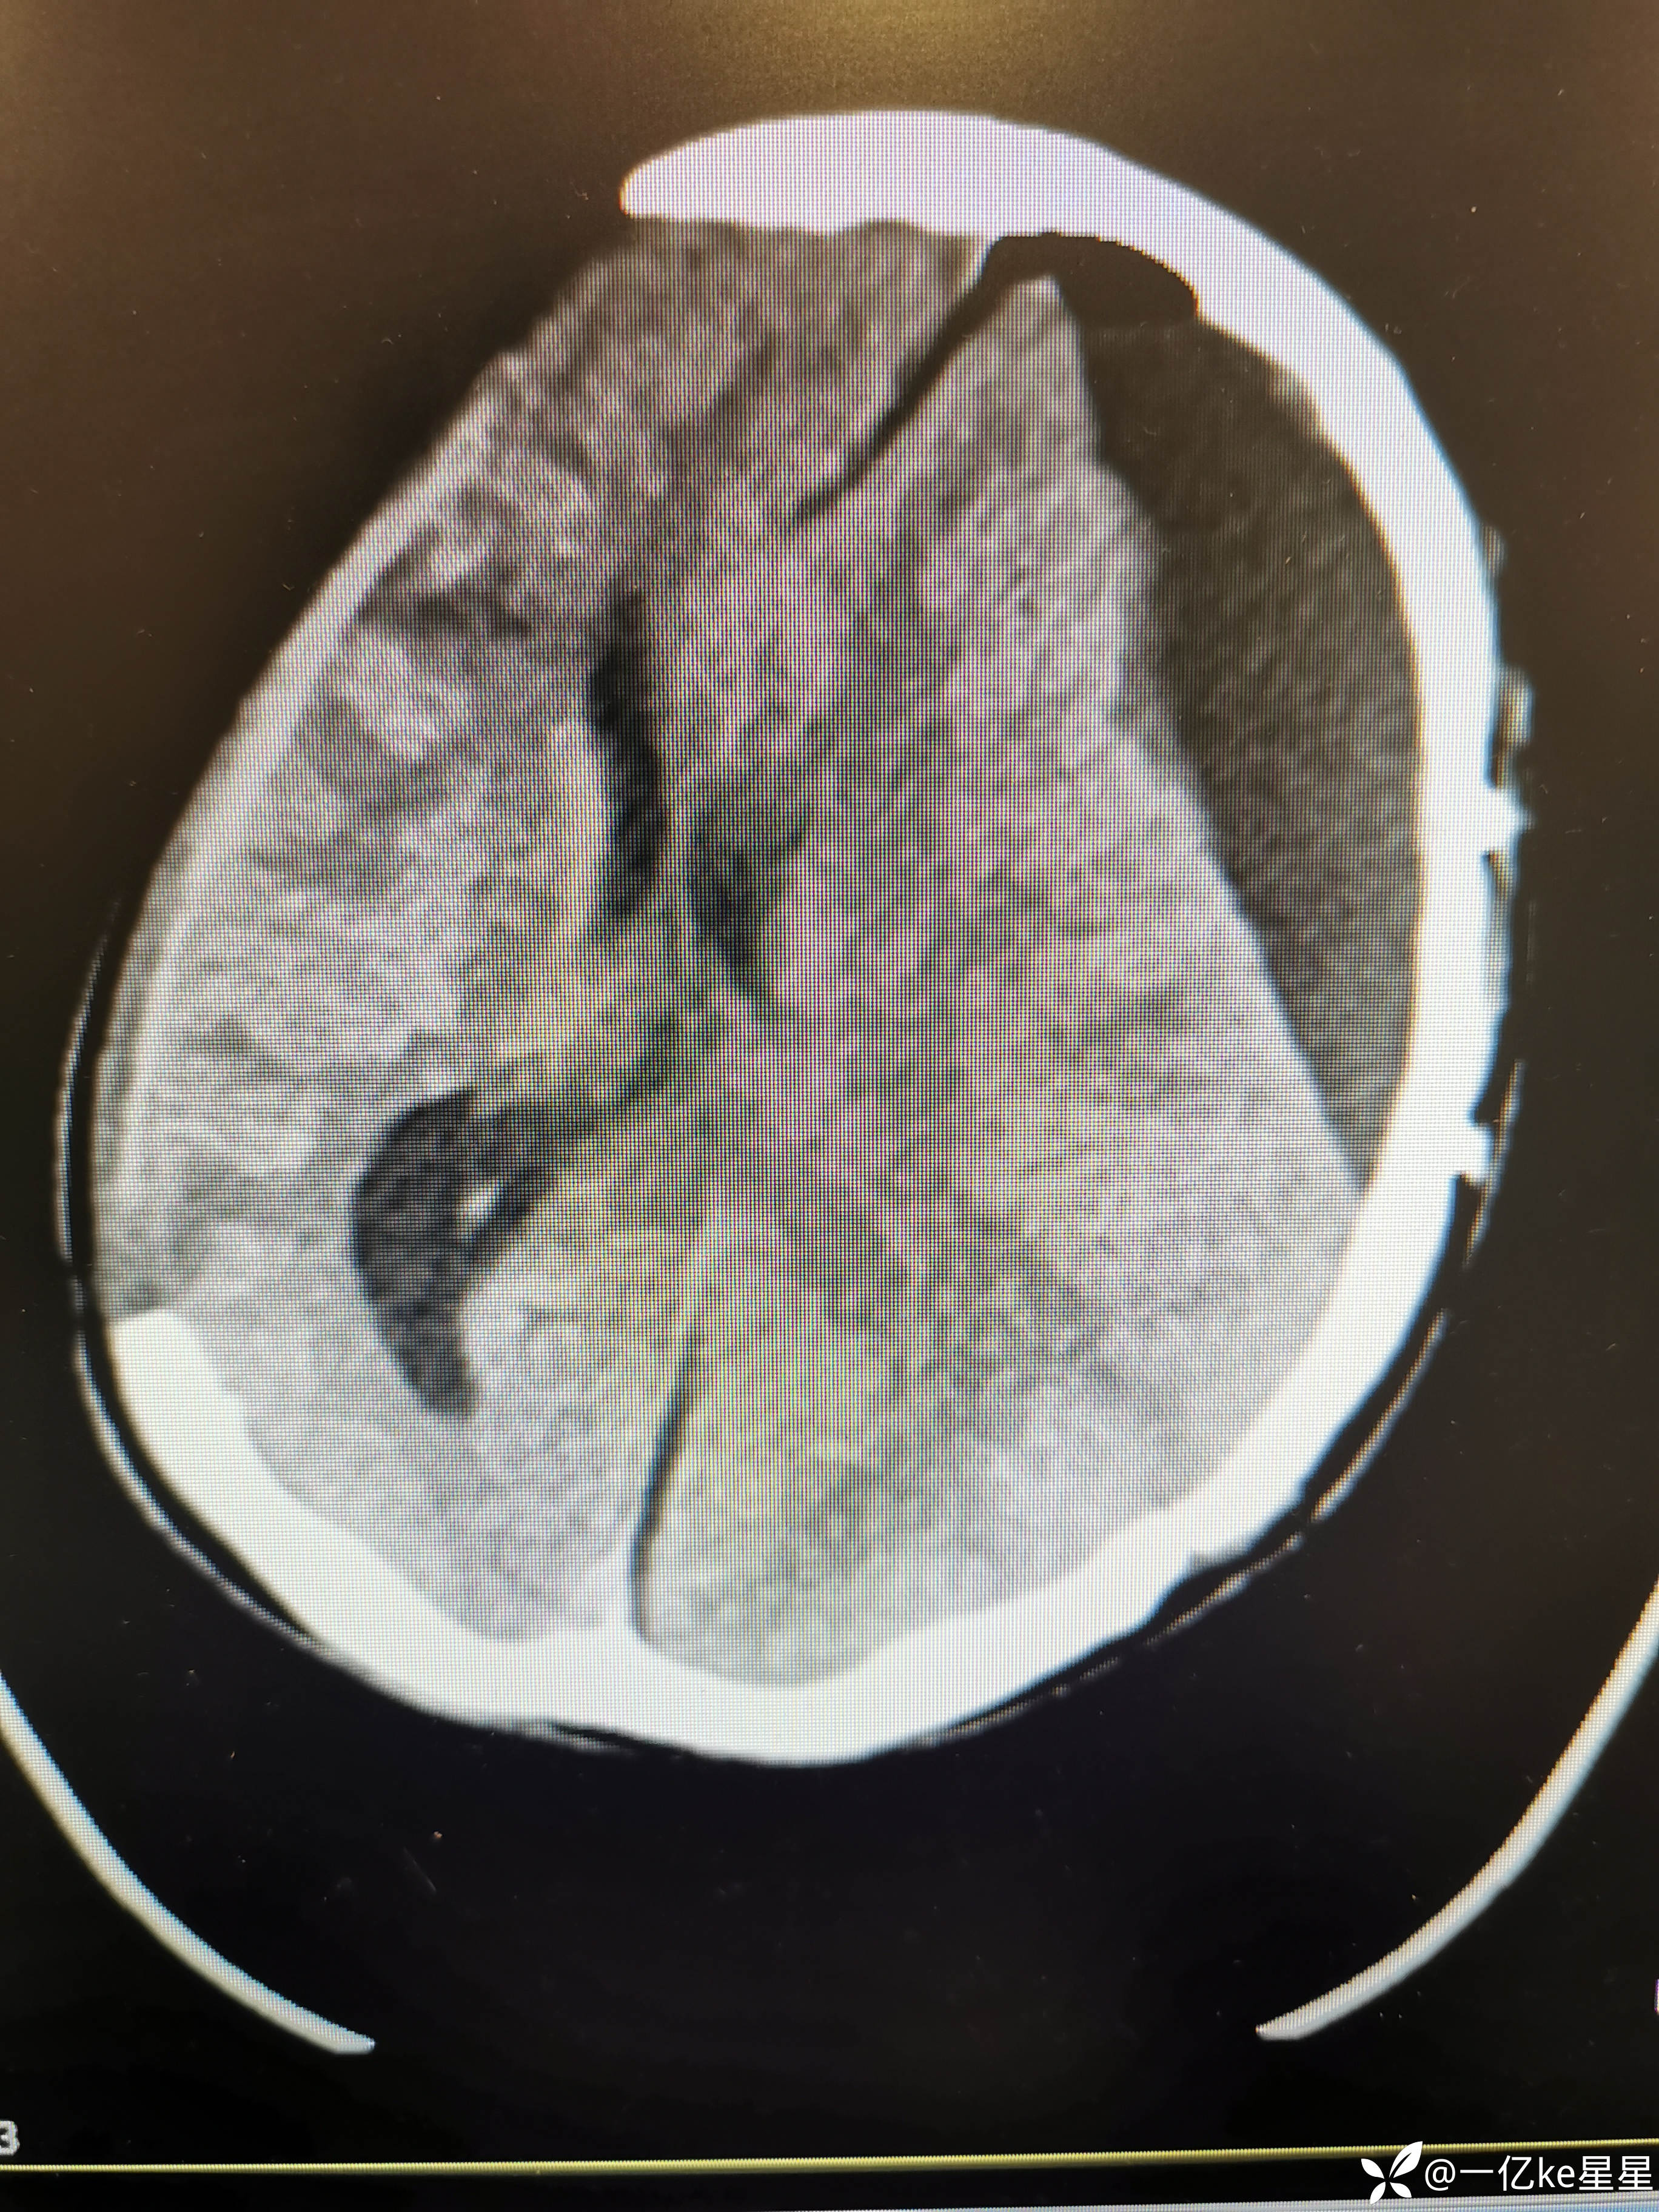

医者超哥等 2人推荐患者车祸伤致意识障碍50余天。当地查头颅CT:脑出血、急性硬膜下血肿,当地行颅内血肿清除术+去骨瓣减压术,患者意识昏迷,行气管切开,术后复查对侧再次出血,遂再次行颅内血肿清除术,术后对症治疗(具体不详),后患者意识恢复差,间断体温高、心率快,为求进一步治疗,就诊于我院,考虑患者左侧硬膜下积液增多(2023.11.7)